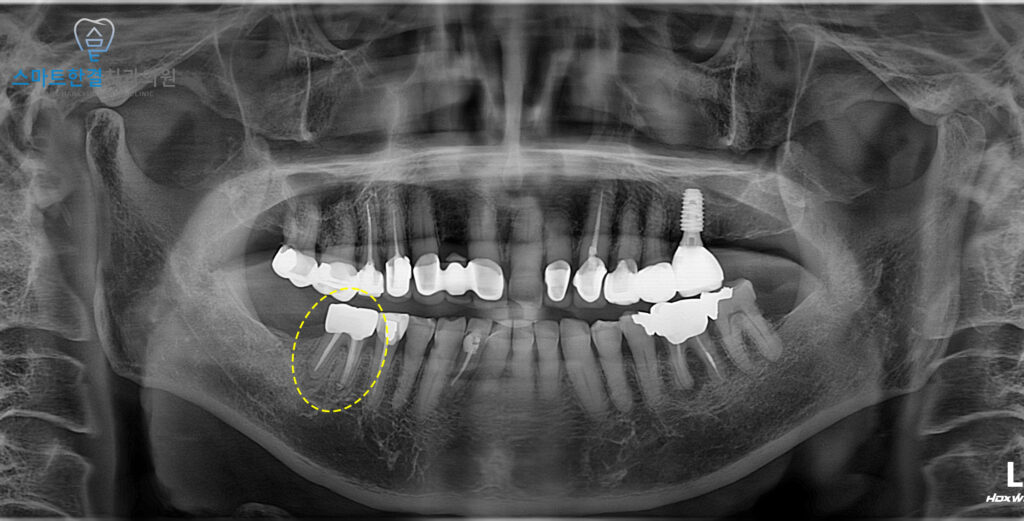

재신경치료를 통해

뿌리 끝에 형성되어 있던

염증이 점차 가라앉으며,

통증과 불편감도 함께 해소되었어요.

치아 주변 잇몸 조직의

염증 반응이 줄어들고,

엑스레이상에서도 치근단 부위의 회복이

확인될 정도로 좋은 결과를 보였답니다.^^

환자분께서는 재신경치료를 통해

뿌리 끝 염증이 없어지고

이로인해, 치아도 더이상 아프지 않아

매우 만족해주셨어요!😊

또한 오래된 보철물도 새롭게 제작하여

기존보다 더 자연스럽고 안정적인 형태로

치아의 기능과 미적인 부분을

모두 개선할 수 있어

좋아해주셨답니다.^^